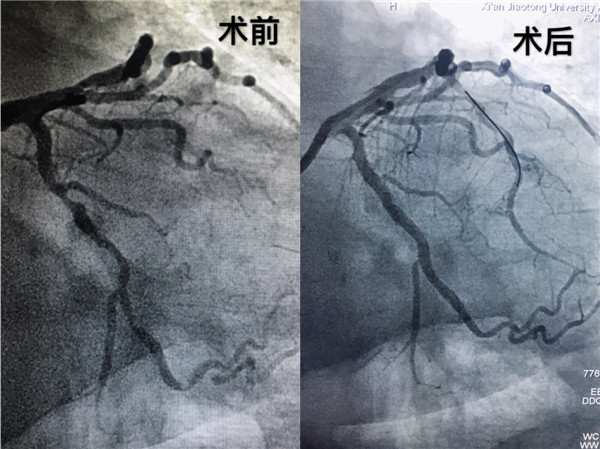

患者女性,63岁,一周前一次外出中感觉胸口闷,气短,并且伴有后背酸痛,自己服了速效救心丸症状缓解,没有引起重视,四天前受凉后症状加重,从阎良急转至我院,邓捷主任医师接诊后仔细观察患者心电图,评估病情,患者属于急症,患者及家属情绪焦灼难耐,邓主任考虑到患者病情及心理状态,决定放弃周末休息时间,带领手术团队为其行冠脉造影术。完善术前准备,造影示冠脉三支血管均存在病变,最严重处堵塞95%,立即为患者前降支植入支架两枚,考虑到患者安全,暂时撤台,转入心内重症监护室继续观察。四日后患者病情稳定,再次行造影术,为了更清晰探查血管内病变,置入OCT导管,术中示患者血管存在纤维斑块、脂质斑块、钙化斑块,血管内血流已是“一线天”的状态。俗话来讲,就好比水管里被沙石堵塞,水管内壁一圈附着了坚硬的水垢,水流艰难的通过一丝小缝隙,可见此患者胸闷、胸痛症状元凶在于此。要想恢复正常的血流,必须克服斑块带来的各种困难。医学圈内一句俗语说得好:“千不怕万不怕,就怕病变有钙化”。而OCT是评价钙化病变面积、深度和体积的金标准。

经过手术团队对图像缜密的研究,为患者右冠脉和左冠脉回旋支植入冠脉支架,血流恢复TIMI 3级,手术耗时一小时余。术后患者症状逐渐减轻,焦虑的情绪渐渐平复。至此,由邓捷主任带领的冠脉团队成功完成我院首例OCT指导下冠脉支架植入术。